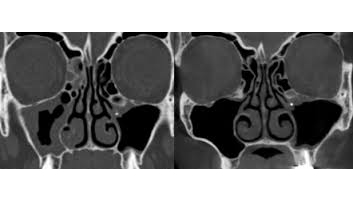

Les applications du cone beam sont nombreuses allant de la chirurgie buccale à l’orthopédie (poignets…) en passant par l’orthodontie, la chirurgie maxillo-faciale et l’ORL. Bien qu’il soit plus pratiqué pour l’examen des sinus, il est de plus en plus utilisé en médecine dentaire. Etant plus indiqué pour l’examen des tissus minéralisés (dents, cartilages, os), il permet d’identifier les lésions osseuses, les fractures, les infections, les kystes ou les corps étrangers.